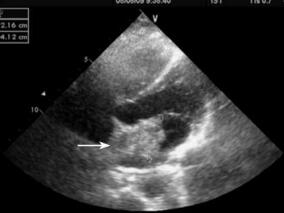

1小时条评论1 病例简介 患者女,37岁,主因发作性意识丧失1次,口齿不清3天于2011年4月25日来我院就诊。患者4天前在爬山时无明显诱因的情况下突然晕倒伴意识丧失,持续约数分钟,同伴诉当时患者双眼紧闭、面色苍白,无大汗淋漓与口唇发紫,无肢体抽搐及舌咬伤,无尿便失禁,...

以晕厥为首发表现的脑栓塞 病因很罕见